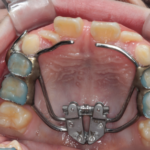

反対咬合(受け口)の症例

Before After 治療途中の小児矯正の症例です。 成長期に上顎の幅を広げ ...